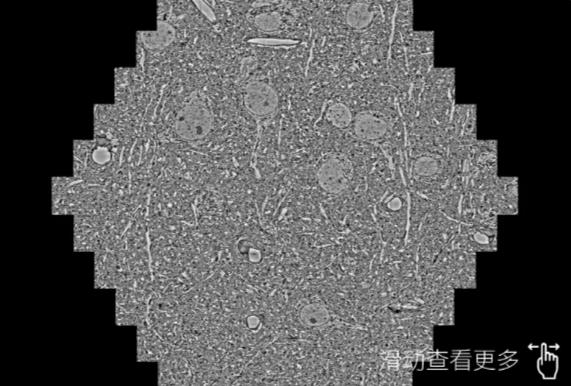

鼠脑切片。左图使用南京蔡司南京扫描电镜MultiSEM706对165μmx143pm面积区域成像,耗时仅需1.5秒。右图为鼠脑切片中30μm区域放大效果。样品由芝加哥大学B.Kasthuri提供。

使用蔡司高速南京扫描电镜MultiSEM对1mm²人脑皮层组织进行高分辨成像,并对其中的各种细胞结构进行三维重构分析。左图展示了2x3mm²组织平面中锥体神经元的三维重构效果。右图显示了局部体积神经元三维重构。图像由哈佛大学chtman实验室提供,渲染图由D. Berger 制作。